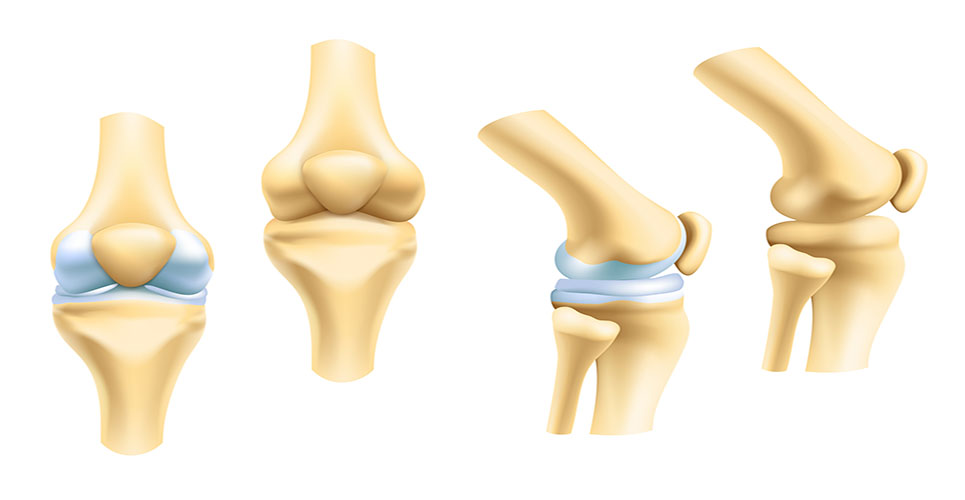

Анатомические рисунки суставов человека